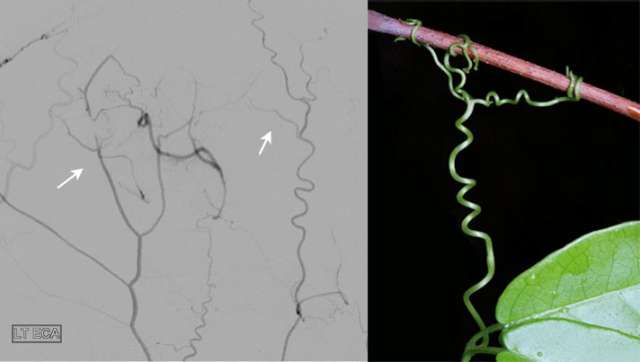

Moyamoya Figure 2

The figure shows multiple new arteries (arrows) growing from the scalp to the brain after an EDAS surgery in a patient with narrowing of the intracranial arteries. The arteries growing from the scalp resemble the tendrils of a vine reaching to supply additional blood to the brain.